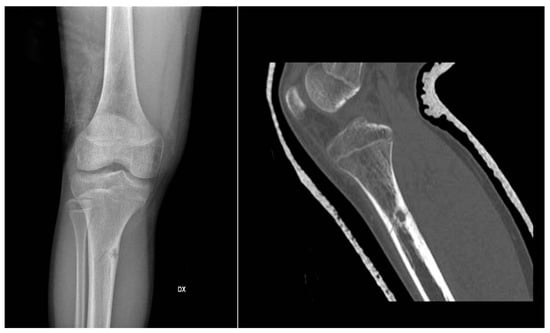

Figure 1. X-rays and CT scan of a tibial fracture that occurred in the development site of an Osteoid osteoma.

In X-ray examination, a bone-forming tumor appears as a nidus surrounded by sclerotic tissue. It may be hard to identify when it is intra-articular, therefore requiring further look examination. The second-level exam is a CT scan, which displays a small, defined nidus surrounded by a sclerotic reaction which may contain calcifications. Bone scintigraphy usually shows arterial phase uptake in the nidus due to its high vascular concentration and lower concentration in the reactive surrounding bone. There is a typical sign called the double-density sign which is diagnostic. It is fundamental to pay attention to growth plates since they can obscure the signal if the osteoid osteoma is in their proximity; therefore, it can be helpful to evaluate the contralateral side. Other imaging techniques may help the diagnostic workup, but those must be considered case by case [19,20,21] (Figure 1).